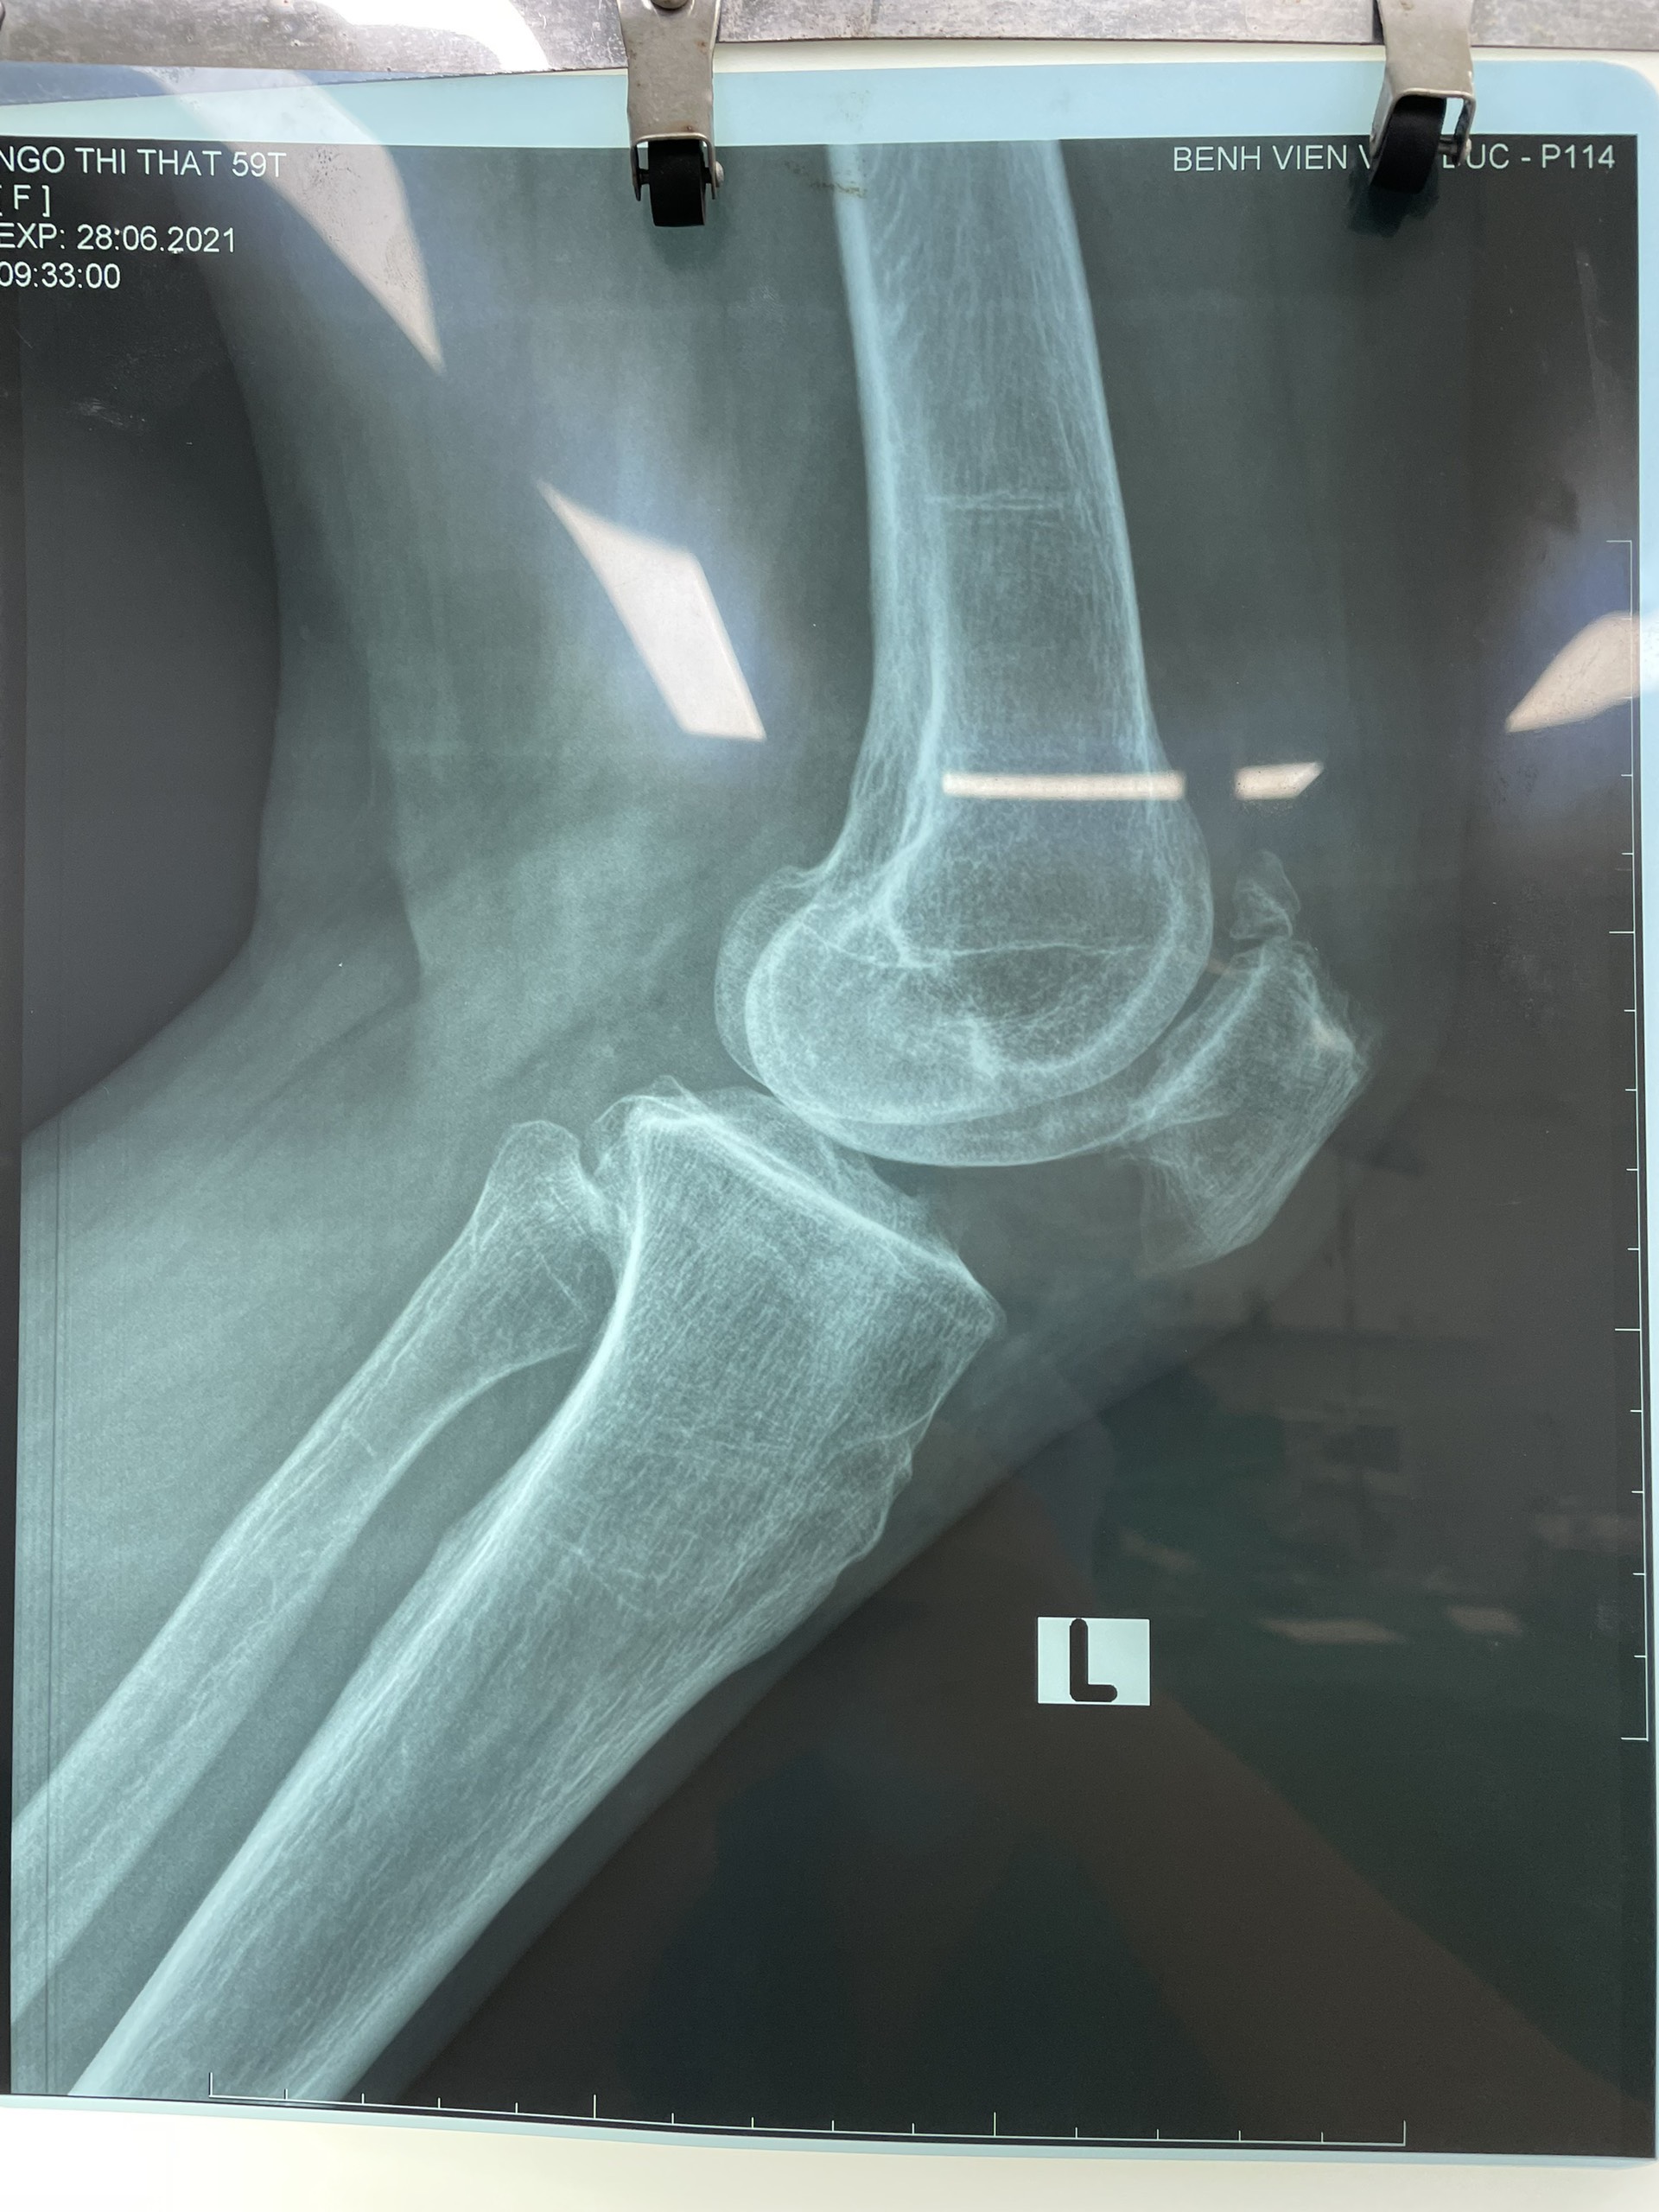

Hình ảnh x-quang 2 khớp gối trước mổ

Tại đây, các bác sĩ thăm khám lâm sàng có biểu hiện tràn dịch khớp gối mức độ vừa, biên độ vận động gối bình thường, không có mất vững gối, không có triệu chứng lâm sàng của tổn thương sụn chêm. Chụp phim Xquang thấy có tổn thương mất liên tục của xương bánh chè phía trên ngoài, siêu âm có tràn dịch khớp gối. Chẩn đoán sơ bộ bệnh lý xương bánh chè hai mảnh hai gối vì không có yếu tố chấn thương. được chụp phim cộng hưởng từ đánh giá các dây chằng, sụn chêm và sụn khớp đều thấy bình thường. Tổn thương cực trên của hai gối nghĩ đến thương tổn xương bánh chè hai mảnh.